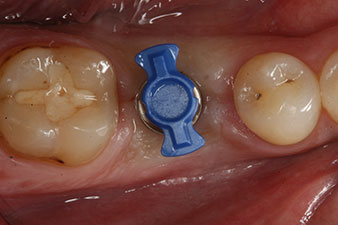

Nach gründlicher Entfernung des Granulationsgewebes wurde das Implantat wie geplant eingebracht (blueSky, bredent).

Das Drehmoment beim maschinellen Einbringen war 43 Ncm. Zusätzlich wurde, nach Einschrauben eines speziellen, auf das Implantatsystem abgestimmten Mess-Pfostens (SmartPeg), der ISQ-Wert mit der Sonde des W&H Osstell ISQ Modul bestimmt.

Dieses Modul ist für das Implantmed von W&H optional erhältlich und wird an den Implantologiemotor gedockt (vgl. Abb. 11). Der dimensionslose ISQ-Wert war direkt bei der Insertion 64 in oro-vestibulärer und 68 in mesio-distaler Richtung (Maximalwert = 100). Dies hätte eine offene Einheilung oder sogar Sofortversorgung erlaubt.

Wegen des unzureichenden Knochens krestal am Implantat wurde der Bereich mit den bei der Präparation des Implantatlagers gesammelten Knochenspänen augmentiert und speicheldicht vernäht.